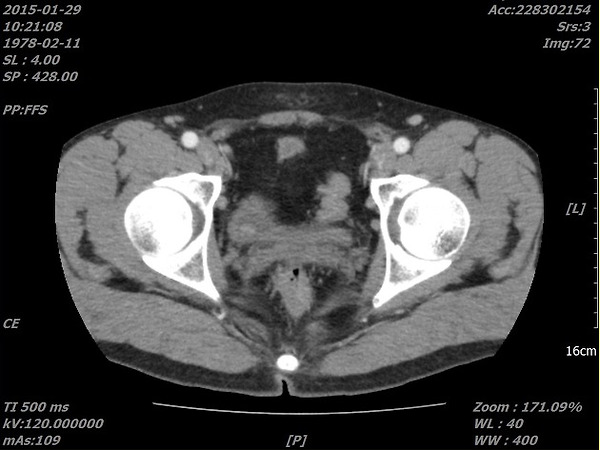

위사진은 암으로 추측되는부분이라도 개인병원 의사가 찾아주신 자료 중 하나입니다.

이게 맞을까요? 첫번째  2011년, 그다음 2015년 세번째도 2011년 그다음 2016년입니다. ....

올려주신 영상은 PELVIS 쪽의 조영증강(ENHANCED) CT 검사네요.

첫째, 셋째 사진이 2011(초진검사) 하신 영상이고,

둘째 ,넷째 사진이 15,16년 사진이시죠.

사진이 명확치 않아 확인지 조금 어렵지만

사진상에 보이는 것은 네번째 마지막 사진에만 확실한 종양의심부분이 관찰이 되고 있습니다.

추가질문  「 좀 더 선명한 사진인데....다시한번 봐주시겠습니까..... 」 에 대한 답변입니다.

아. 정확히 보이시네요.

첫번째 사진 2011년 4월22일 ENHANCE CT 영상에서도

동그라미 쳐진 부분(화살표) 부분이 조영증강된 것이 확인이 됩니다.

나머지도 보시기 쉽게 동그라미 표시를 해드렸습니다.